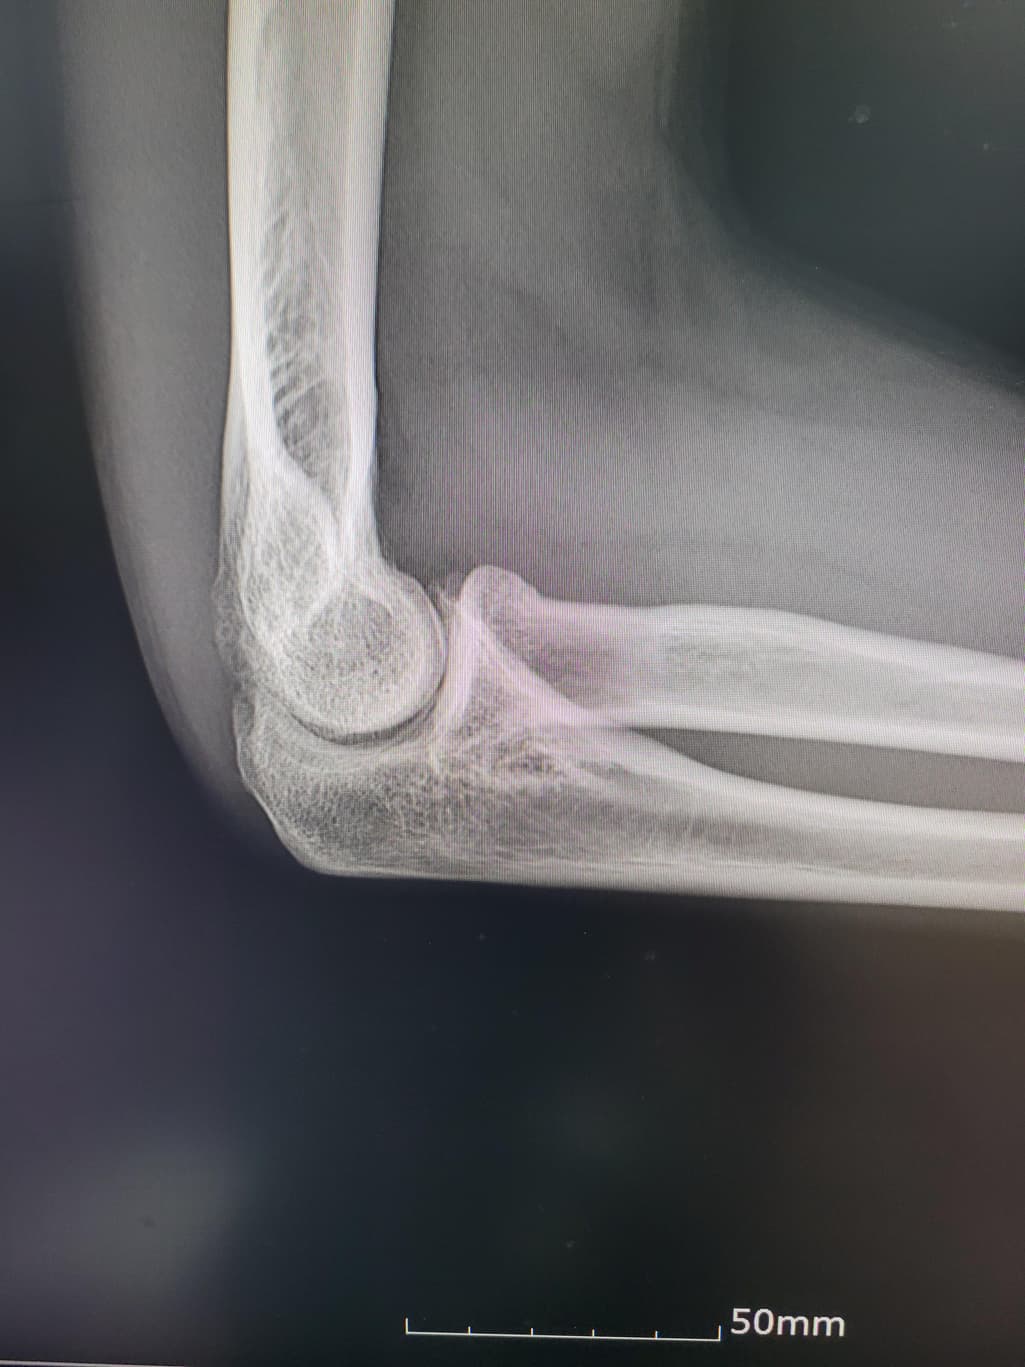

이거 활액막연골종인지좀 봐주세요(x-ray 첨부)

팔이 아파서 여러병원 찾아다니느라 엑스레이 사진도 복사해왔는데 1,2년 전에 비해서 팔꿈치에 동그란 게 생겼더라구여 이게 뭔지 모르겠습니다

과거에 활액막연골종으로 같은 부위를 수술받은 적이 있습니다

첫 번째 두 번째 사진이 가장 최근입니다

활액막연골종은 일반적으로 엑스레이에서 뼈의 경계가 부풀어 오르거나 변형된 모습이 나타날 수 있습니다.

엑스레이에서 종양은 종종 비정상적인 경계와 불규칙한 모양을 보입니다 뼈의 구조와 혼합된 모습 일 수 있습니다.